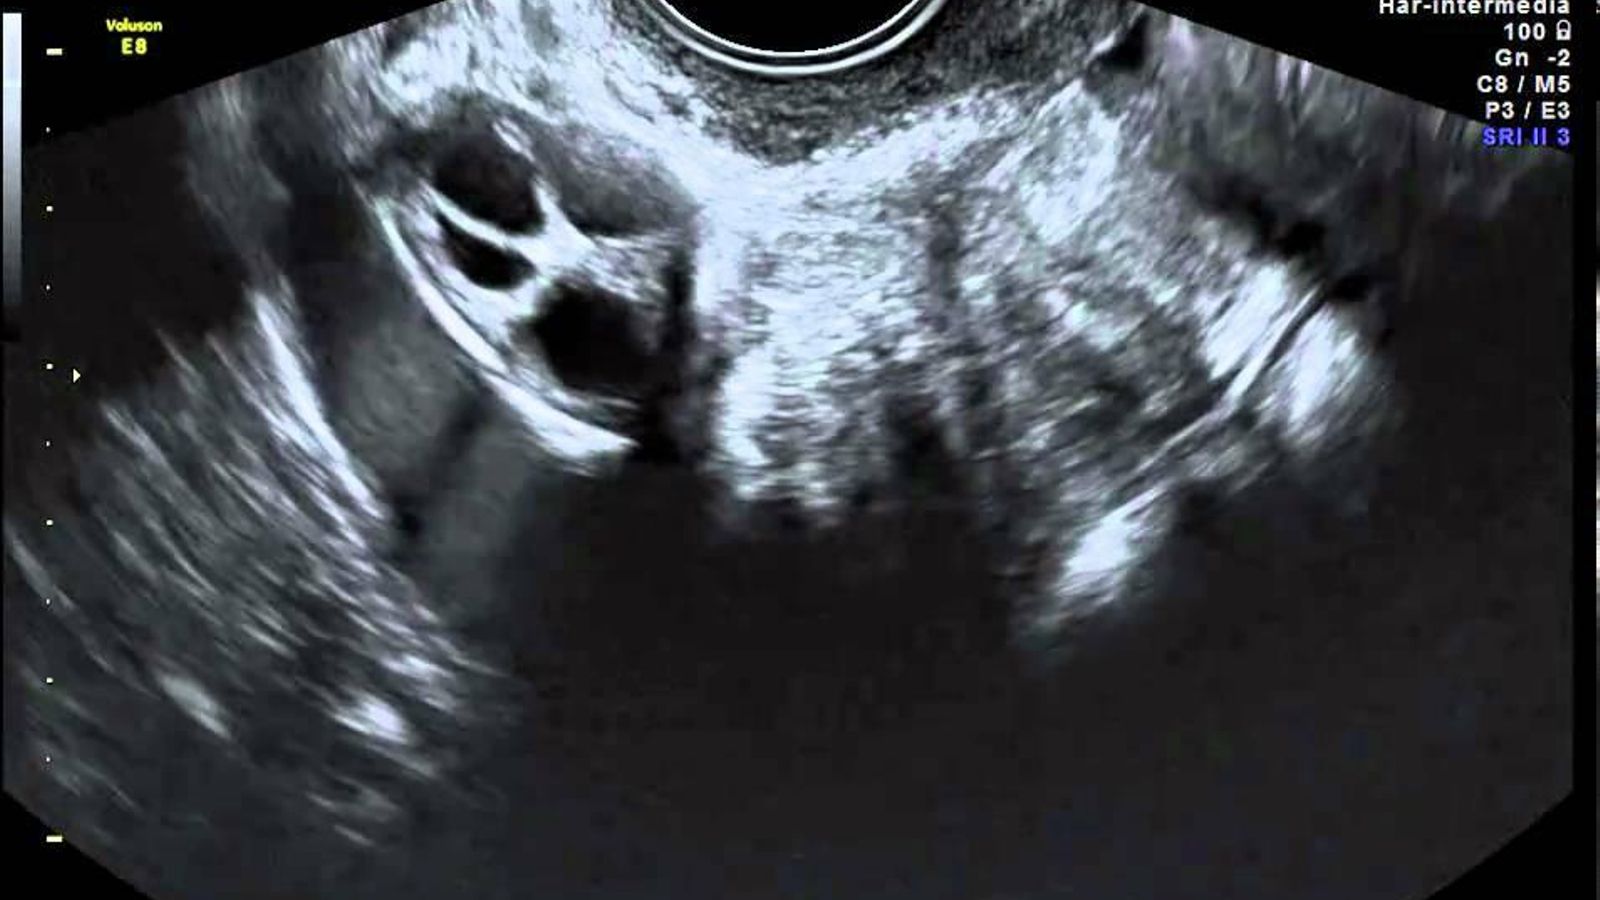

Monitoreo por ultrasonido

Monitoreo de ultrasonido

Después de la ovulación, la cavidad llena de líquido (quiste folicular), que contenía el huevo, se colapsa. Este colapso es una presunta evidencia de ovulación y puede detectarse mediante ecografías diarias en serie. Este método, sin embargo, es costoso y requiere mucho trabajo. La ovulación también puede ocurrir incluso sin colapso folicular. Por estas razones, este método de detección de la ovulación no se utiliza de forma rutinaria.